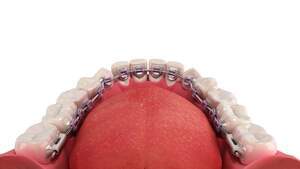

裏側の矯正中の歯の裏側を歯科用鏡で映したイラスト

裏側矯正は舌側矯正、リンガル矯正とも言います。歯の裏側にブラケットとワイヤーを付けるため外からは見えない矯正方法で、「矯正をしていることを知られたくない」「目立たずに歯列矯正をしたい」という方におすすめです。

フルリンガルは上下全ての歯の裏側にブラケットを装着し、ワイヤーを通して歯を移動させる矯正方法です。

裏側矯正で使用する歯の裏側にブラケットとワイヤーを装着した歯のイメージ

また、フルリンガルは表側矯正と比べて虫歯になりにくいというメリットもあります。歯の裏側はエナメル質が厚く、下の歯は唾液腺が近く唾液の循環が行き届くためです。